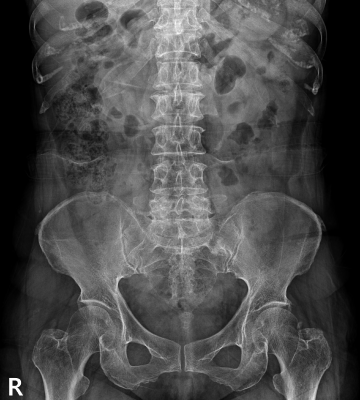

척추전방전위증 수술 전·후

2022.09.21

2022.12.30

ㆍ환자 동의를 받은 자료이며, 이미지 사진은 실물과 다를 수 있습니다.